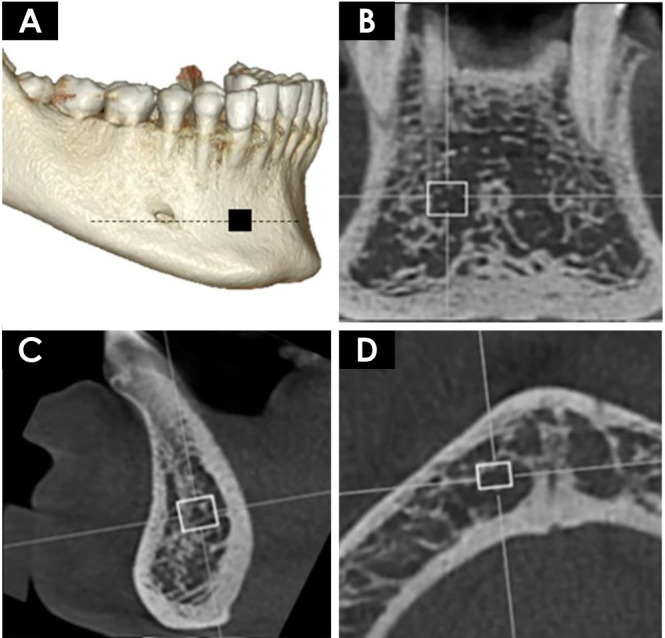

Purpose: This study aimed to evaluate the influence of different cone-beam computed tomography (CBCT) image reconstruction parameters (slice thickness, noise filter application and orthogonal plane) on the calculation of bone fractal dimension and, based on those findings, to determine the optimal protocol for this type of assessment.

Materials and methods: The sample consisted of 18 patients who underwent CBCT scans of the mandible and bone densitometry examinations. Four mandibular regions of interest were selected from the scans, with various image reconstruction parameters applied. Fractal dimension was calculated using the box-counting method. Two independent observers performed the evaluations, and all analyses were conducted with a significance level of 5%.